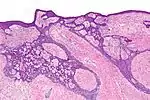

| Morpheaform basal-cell carcinoma (also known as "cicatricial basal-cell carcinoma", and "morphoeic basal-cell carcinoma") | Narrow strands and nests of basaloid cells, surrounded by dense sclerotic stroma.[25] | Aggressive[22]:748[23]:647 | ![]() |

| Superficial basal-cell carcinoma (also known as "superficial multicentric basal-cell carcinoma") | Occurs most commonly on the trunk and appears as an erythematous patch.[22]:748[23]:647 | ![]() | |